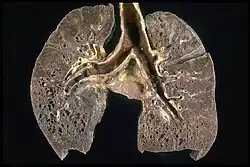

Histopathology

Sarcoidosis is characterized by the formation of non-necrotizing ("non-caseating") granulomas in various organs and tissues.[95] Giant cells, specifically Langhans giant cells, are often seen in sarcoidosis.[96] Schaumann bodies seen in sarcoidosis are calcium and protein inclusions inside of giant cells as part of a granuloma.[97] Asteroid bodies can be seen in sarcoidosis.[97] Hamazaki–Wesenberg bodies can be seen in lymph nodes and more rarely in lung biopsies with sarcoidosis and are inclusion bodies of lysosomes with protein, glycoprotein and iron.[98]